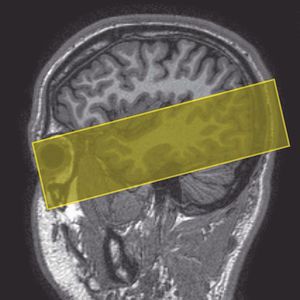

Axial oblique imaging of the temporal lobes. Slices are angled parallel to the temporal lobe (Westbrook C., 2014)